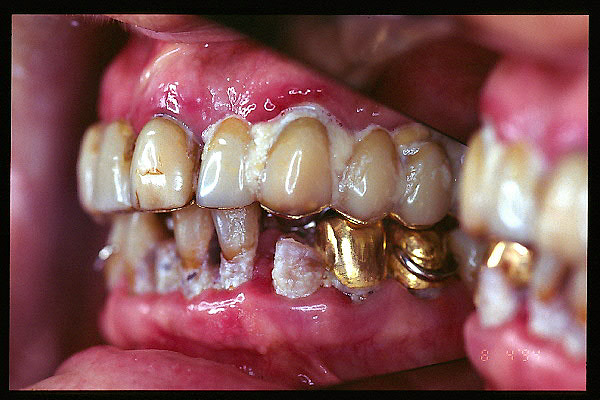

CM Caries, patología periodontal, desgaste.